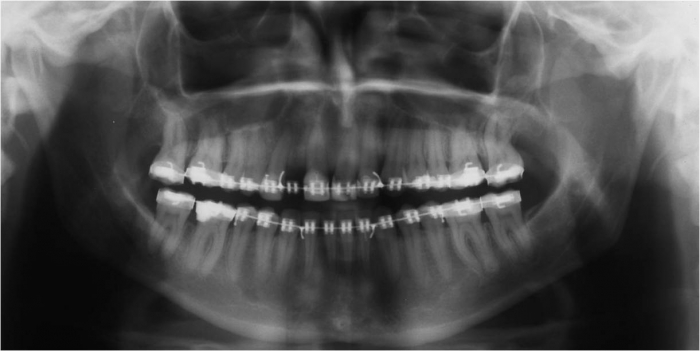

Raio X após cirurgia ortognática de avanço de maxila - Clínica Cliniface

Raio X após cirurgia ortognática de avanço de maxila